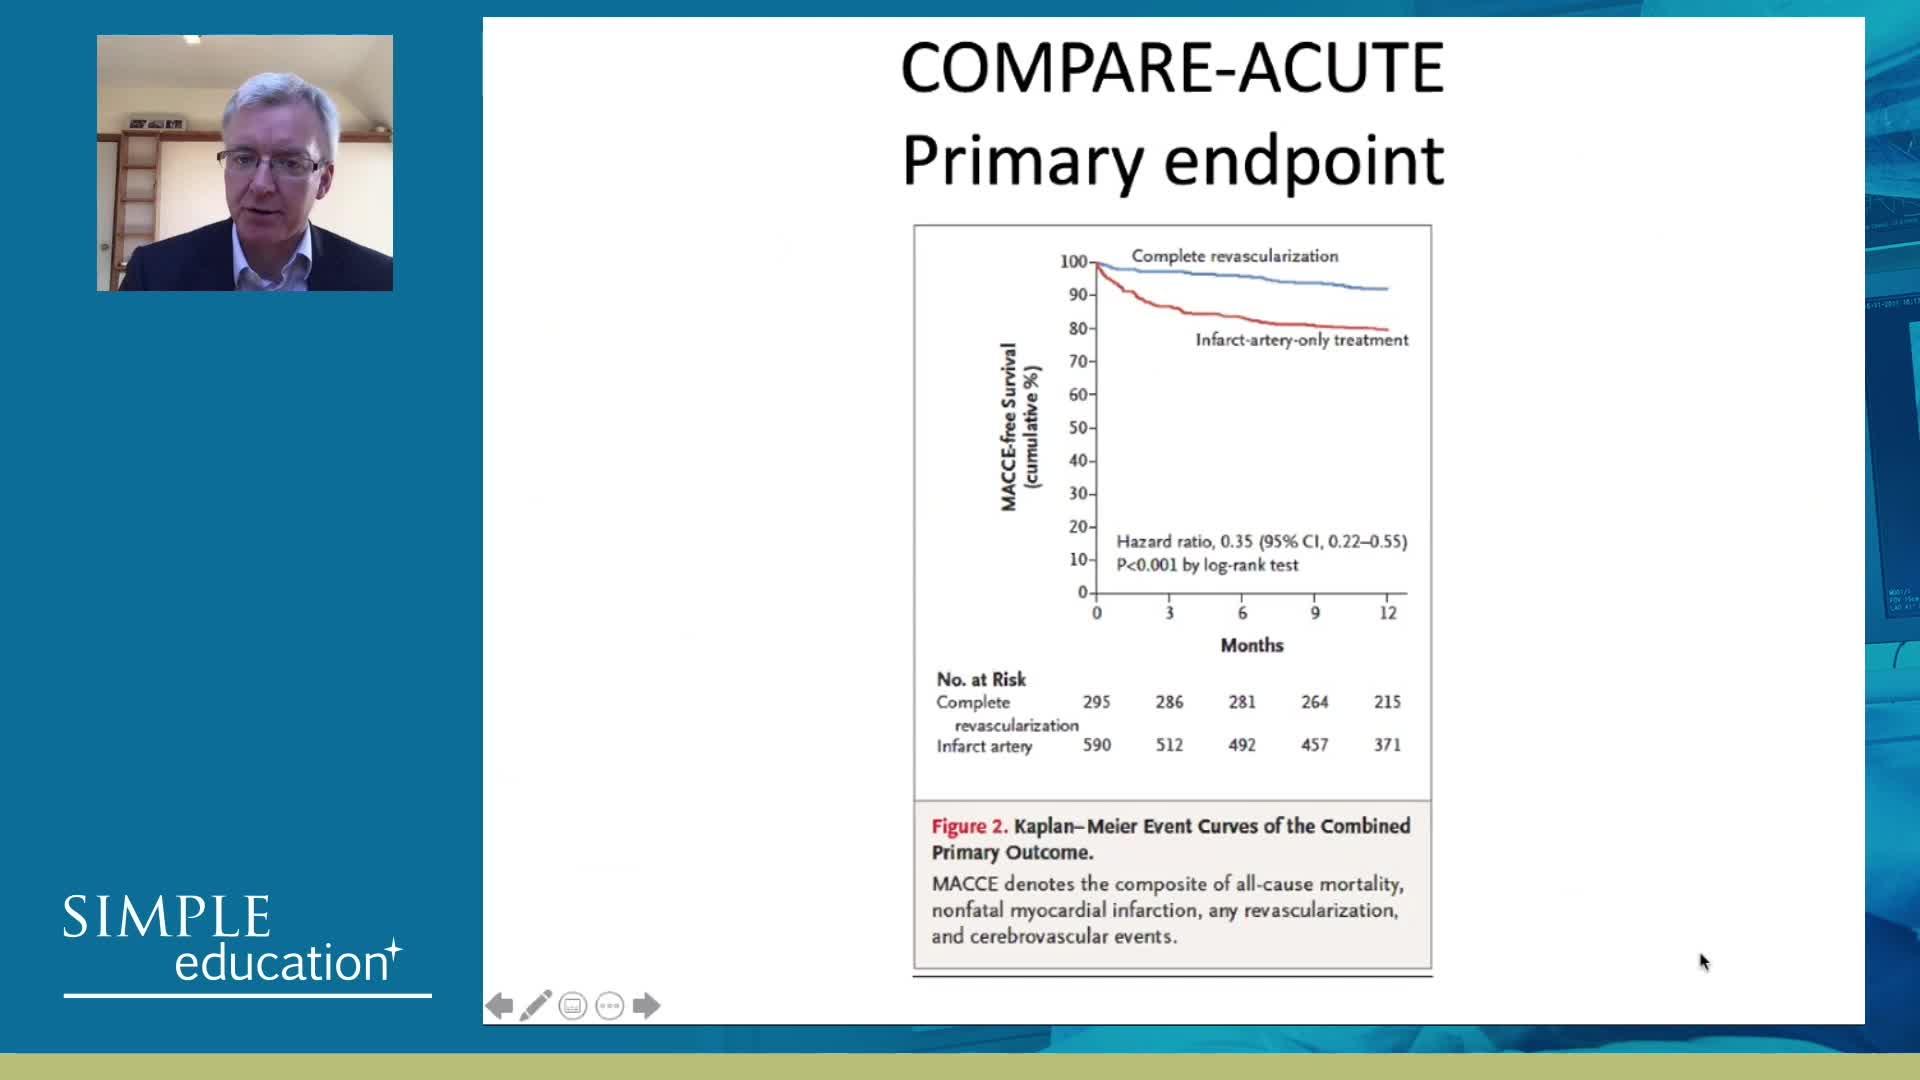

Spotlight Discussion: Management of multivessel disease in patients with acute coronary syndromes

Intracoronary guidance in acute coronary syndromes - Dr Hernan Mejia-Renteria